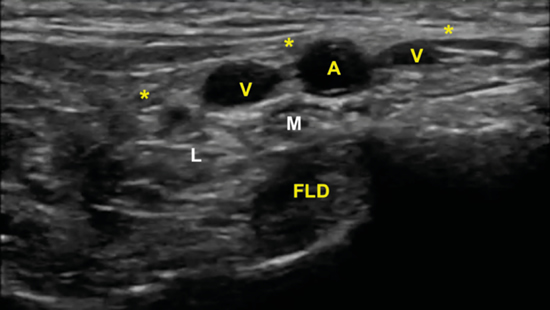

Figura 11. Imagen sonográfica de la diferenciación del nervio plantar medial (M) y del nervio plantar lateral (L) debajo de la arteria y venas (A, V) y sobre el tendón flexor largo del primer dedo (FLD). En superficie el retináculo flexor (*).

La imagen sonográfica se centrará en el espacio situado bajo la fascia profunda del músculo abductor del primer dedo, por donde discurrirán los haces neurovasculares plantar medial y plantar lateral, diferenciados y separados por el septo de Heimkes o interfascicular3. El nervio plantar medial se muestra con mayor sección que el nervio plantar lateral, y las venas laterales con mayor luz que las mediales (Figura 14).